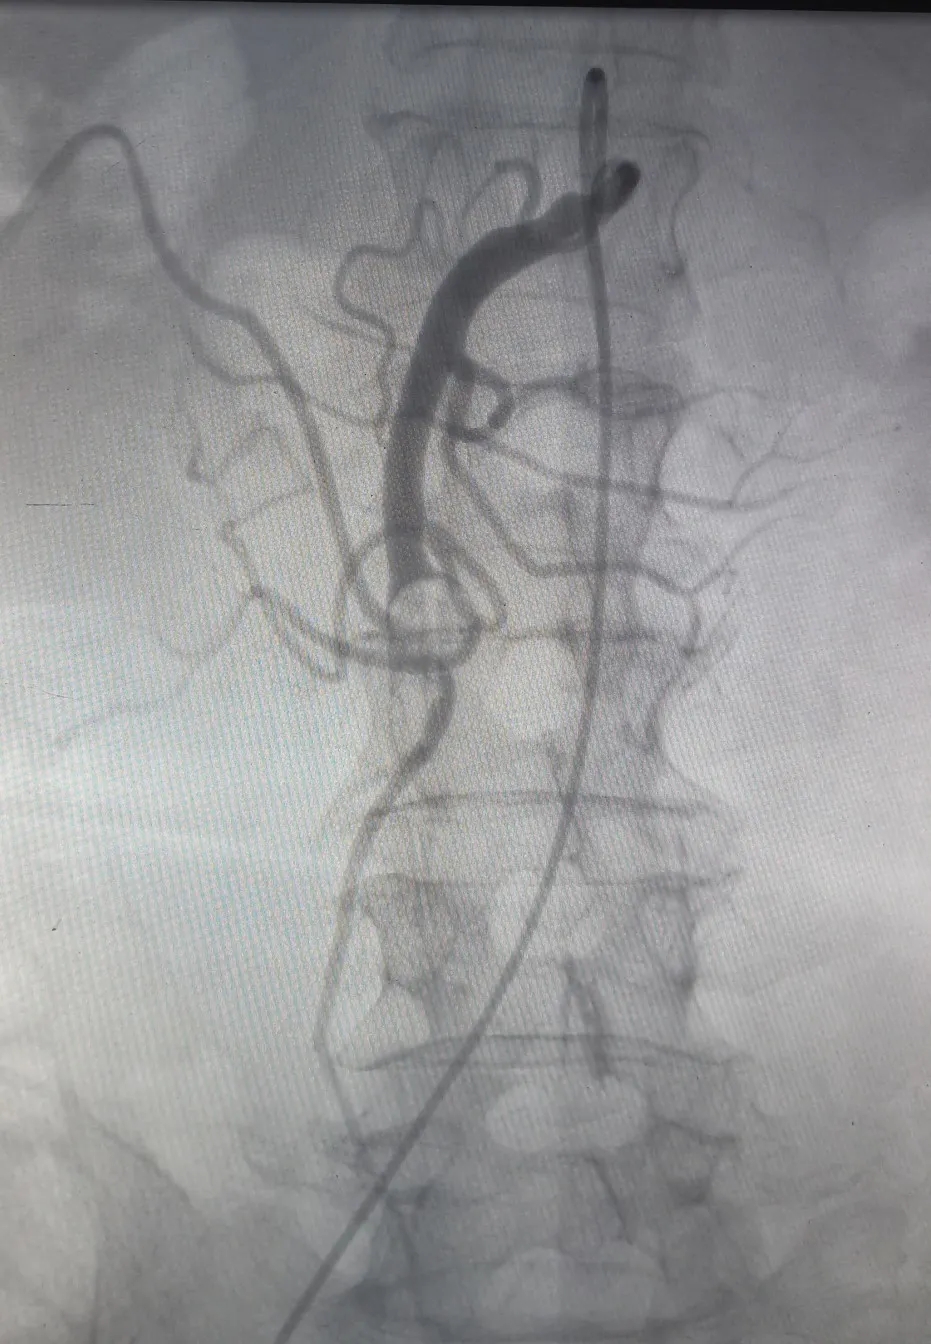

▲肠系膜上动脉栓塞吸栓术前后对比